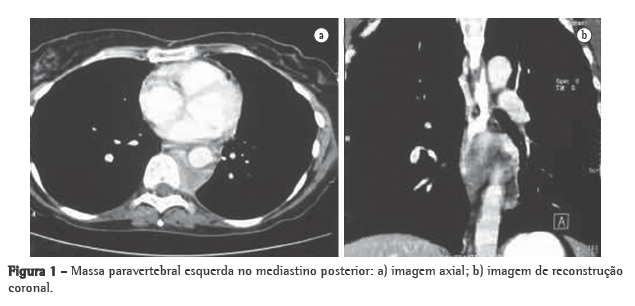

Uma paciente de 49 anos de idade, fumante inveterada por 30 anos (30 anos-maço) com tosse crônica, buscou atendimento médico, apresentando dispneia e dor torácica há 2 anos. Ela era HIV negativa. Seu histórico médico incluía tratamento de TB pulmonar (4 anos antes) e pneumonia recorrente (4 episódios nos últimos 4 anos), bem como dor no pescoço e linfoadenomegalia (2 anos antes, com resolução espontânea). A TC, sem o realce de contraste, revelou uma massa paravertebral à esquerda (diâmetro, 6,0 cm), localizada no mediastino posterior (Figura 1), e mostrou que os pulmões estavam limpos. A lesão estava em extrema contiguidade à aorta descendente e estruturas ósseas, com sinais de crescimento invasivo. A paciente foi submetida à ressecção cirúrgica da massa. As peças cirúrgicas incluíram um fragmento amarelado de 5,0 cm e um nódulo branco de 1,5 cm (identificado como um linfonodo para-aórtico), juntamente com linfonodos do hilo esquerdo e ligamento pulmonar. Microscopicamente, o fragmento maior e o linfonodo para-aórtico exibiam tecido fibroso e adiposo, juntamente com infiltrado inflamatório crônico no qual havia a predominância de linfócitos e células plasmáticas maduras. Grandes histiócitos com pálido citoplasma foram achados comuns, bem como áreas esparsas de agregação e imagens sugestivas de emperipolese (Figura 2a). Estes achados iniciais sugeriam um diagnóstico de DRD, e foi recomendada a confirmação por imuno-histoquímica. Os procedimentos imuno-histoquímicos foram realizados em um laboratório de referência e confirmaram este diagnóstico, com base na análise dos grandes histiócitos, nos quais observamos a expressão de S-100 (Figura 2b) e CD68, embora não tenha sido detectada reatividade para CD1a. Cadeias kappa e lambda estavam expressas em células plasmáticas, enquanto CD20 e CD3 estavam expressas em linfócitos maduros. Não havia tecido linfóide residual no fragmento maior ou no nódulo para-aórtico. Os linfonodos ressecados do hilo esquerdo e ligamento pulmonar não foram afetados. Nenhum tratamento adicional foi administrado após a cirurgia. A paciente foi acompanhada por 12 meses, queixando-se de tosse discreta e dor torácica. O acompanhamento por imagem não detectou recorrência, e nenhuma linfadenomegalia cervical foi observada após a cirurgia. Os testes de função pulmonar (espirometria) realizados à época do diagnóstico do tumor e seis meses após a remoção do tumor revelaram um padrão levemente restritivo.